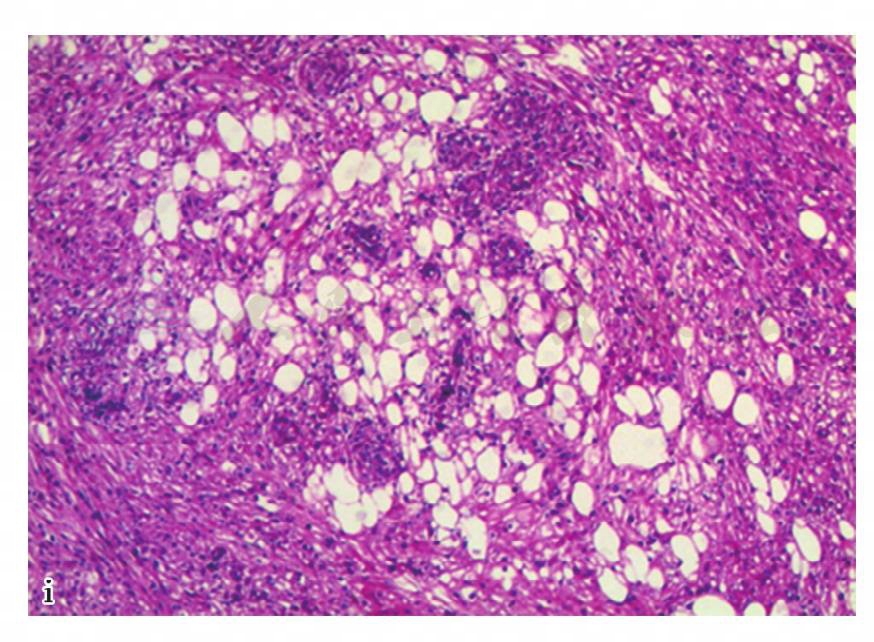

图16 i,病理诊断:右肾血管平滑肌瘤